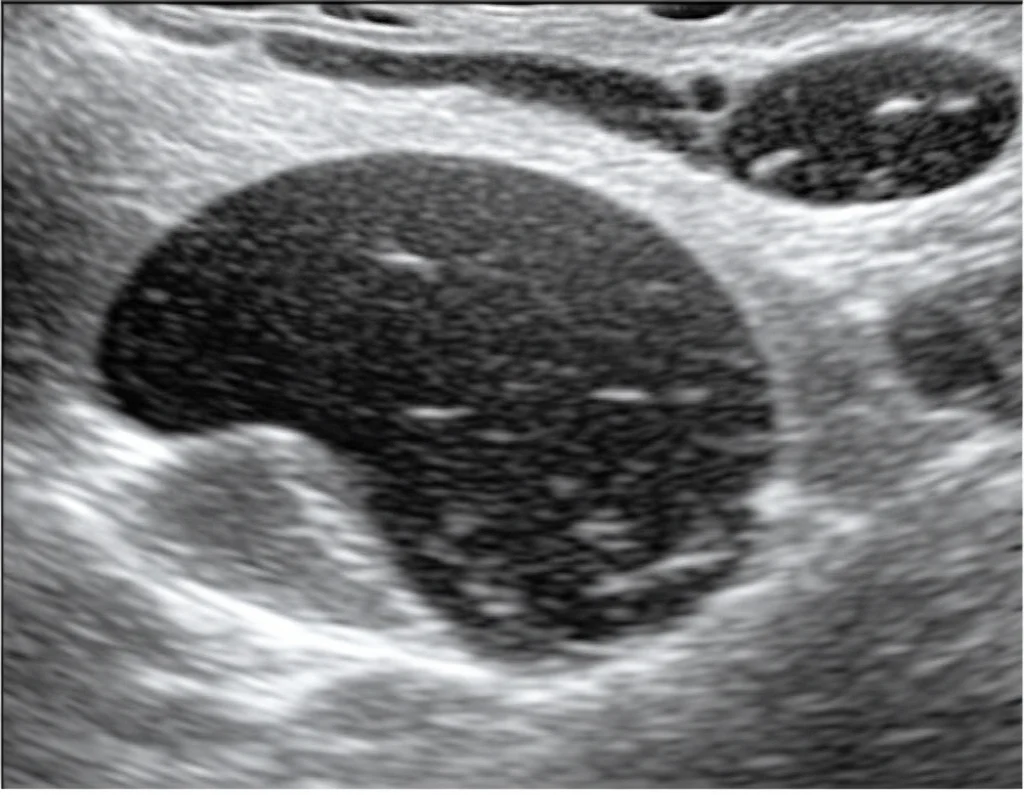

L’ecografia tradizionale (la cosiddetta B-mode US) è spesso il primo passo. È comoda, non costa una fortuna e ci dà già diverse informazioni importanti sulla dimensione e la struttura dei linfonodi. Tuttavia, diciamocelo, a volte distinguere lesioni complesse solo con l’ecografia standard è un bel rompicapo. Ci sono situazioni in cui l’immagine non è abbastanza chiara per darci una risposta definitiva. E qui entrano in gioco le tecnologie più avanzate.

- Linfonodi Benigni: Nella maggior parte dei casi (infiammazioni, iperplasie reattive), il contrasto arrivava prima al centro del linfonodo e poi si diffondeva verso la periferia. Questo pattern è chiamato centrifugo. È come se il sangue entrasse dalla “porta principale” (l’ilo vascolare, spesso centrale) e si distribuisse ordinatamente. Inoltre, raramente presentavano “buchi” nella perfusione (difetti di perfusione).

- Difetti di Perfusione: Un altro indizio importante! Circa il 63% dei linfonodi maligni mostrava aree che non venivano raggiunte dal contrasto (difetti di perfusione), probabilmente a causa di necrosi o vasi sanguigni immaturi e malfunzionanti tipici della crescita tumorale rapida. Nei linfonodi benigni, questo accadeva solo nell’11% dei casi.